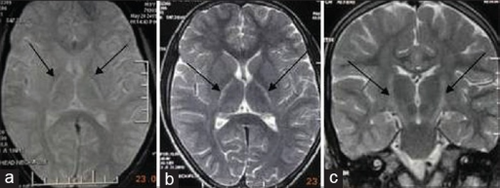

| An MRI with increased signal in the posterior part of the internal capsule that can be tracked to the motor cortex, consistent with the diagnosis of ALS | |

Because symptoms of ALS can be similar to those of a wide variety of other, more treatable diseases or disorders, appropriate tests must be conducted to exclude the possibility of other conditions.[4] One of these tests is electromyography (EMG), a special recording technique that detects electrical activity in muscles.[4] Certain EMG findings can support the diagnosis of ALS.[4] Another common test measures nerve conduction velocity (NCV).[4] Specific abnormalities in the NCV results may suggest, for example, that the person has a form of peripheral neuropathy (damage to peripheral nerves) or myopathy (muscle disease) rather than ALS. While a magnetic resonance imaging (MRI) is often normal in people with early stage ALS, it can reveal evidence of other problems that may be causing the symptoms, such as a spinal cord tumor, multiple sclerosis, a herniated disk in the neck, syringomyelia, or cervical spondylosis.[4]